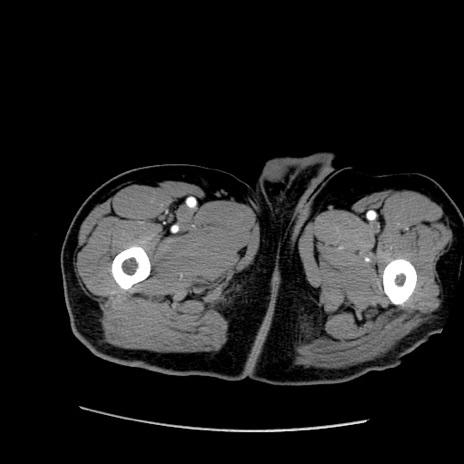

【症例】50歳代男性

【主訴】腹痛

【現病歴】AVMからの被殻出血のため回復期リハ病棟入院中。 本日午後3時頃急に下腹部痛が出現した。

【既往歴】AVM、被殻出血、虫垂炎、高血圧

【身体所見】意識晴明、左半身不全麻痺、会話の理解は良好、36.5°C、腹部:膨隆、全体に板状硬、下腹部正中に圧痛点あり、反跳痛-、筋性防御不明、右下腹部にope scar

【データ】WBC 9400、CRP 0.06